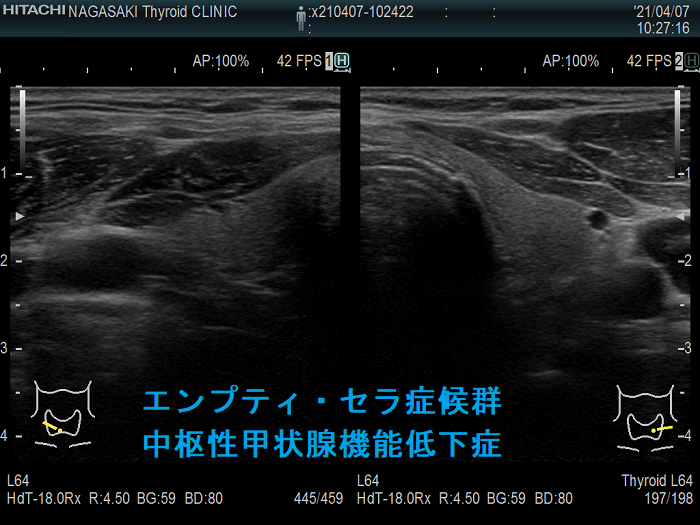

エンプティ・セラ症候群(empty sella症候群, トルコ鞍空洞症候群)は、クモ膜下腔がトルコ鞍内に下垂し、脳脊髄液で満たされた状態。原因は原発性、妊娠、自己免疫性下垂体炎、下垂体卒中、下垂体手術や放射線療法後。症状は視力障害、頭痛、脳脊髄液漏、下垂体機能低下症、中枢性甲状腺機能低下症[視床下部性(3次性)甲状腺機能低下症]、視床下部機能障害、高プロラクチン血症、先端巨大症、クッシング病、SITSH(TSH不適切分泌症候群)を引き起こす事も。原発性甲状腺機能低下症(橋本病・非橋本病)合併が多い。ダイナミックMRIで診断。治療は一般的に外科手術適応外。

中枢性甲状腺機能低下症

エンプティ・セラ症候群(トルコ鞍空洞症候群)による

- 視床下部性(3次性)甲状腺機能低下症(Endocr J. 2009;56(4):585-9.)

エンプティ・セラ症候群(トルコ鞍空洞症候群)の

- 46.42%は原発性甲状腺機能低下症(甲状腺自体が原因の甲状腺機能低下症)

- 26.78%は自己免疫抗体[抗サイログロブリン抗体(TgAb)・抗甲状腺ペルオキシダーゼ抗体(TPOAb)]陽性の潜在性または顕在性甲状腺機能低下症(橋本病)

- 23.21%は自己免疫抗体陰性の原発性甲状腺機能低下症;甲状腺の萎縮

で、中枢性甲状腺機能低下症よりも多い(Clin Exp Med. 2010 Jun;10(2):129-34.)